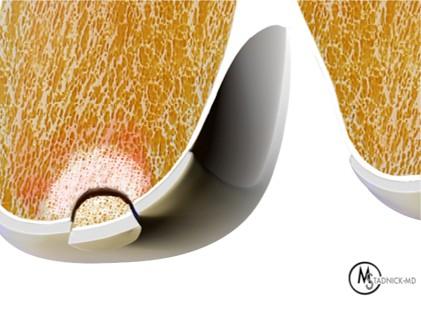

A second method to restore a damaged articular surface is by taking one or more grafts composed of subchondral bone with intact overlying articular cartilage and transferring them into the debrided defect, and then tamping down the graft(s) until the articular surface of the graft tissue is flush with the normal cartilage surrounding the defect (Figure 12). Because the deep aspect of the graft is composed of bone, it has the capacity to heal and incorporate with the surrounding subchondral bone, which stabilizes the graft together with its articular cartilage cap. The transplanted cartilage then functions as the new articular surface. A fibrocartilaginous “weld” typically forms between the cartilage of the grafts with each other and with the surrounding bone, or a thin gap may remain. Autografts are harvested from other sites in the same joint (or sometimes from a different joint in the same patient). Allografts are harvested from cadaver donors.